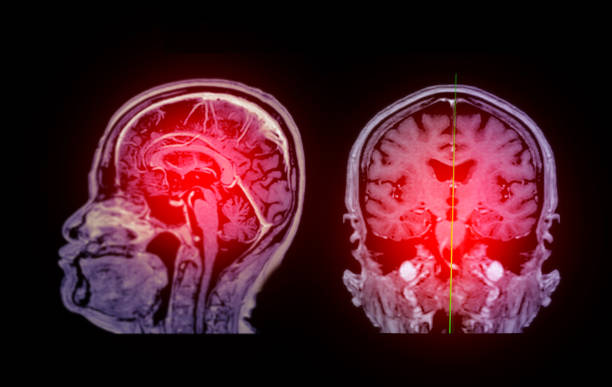

缺血性腦卒中,又稱腦梗死,是一種因腦部血液循環(huán)障礙導(dǎo)致的腦組織壞死疾病。它給患者帶來的不僅是身體上的痛苦,更是心理上的巨大壓力。